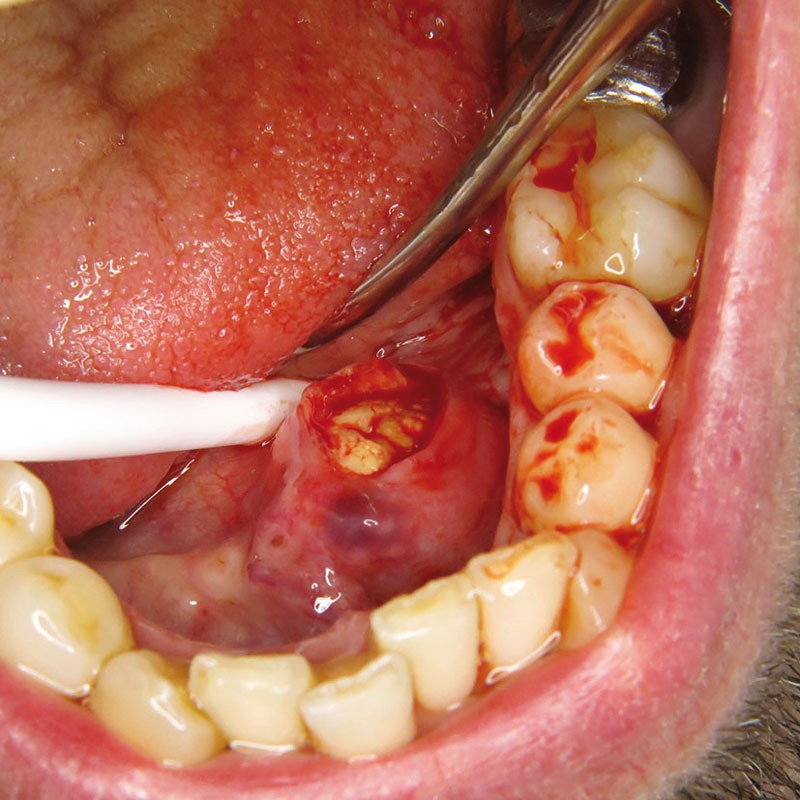

La prise en charge est chirurgicale sous anesthésie locale. Une incision du toit du nodule est réalisée (fig. 4 et 5).